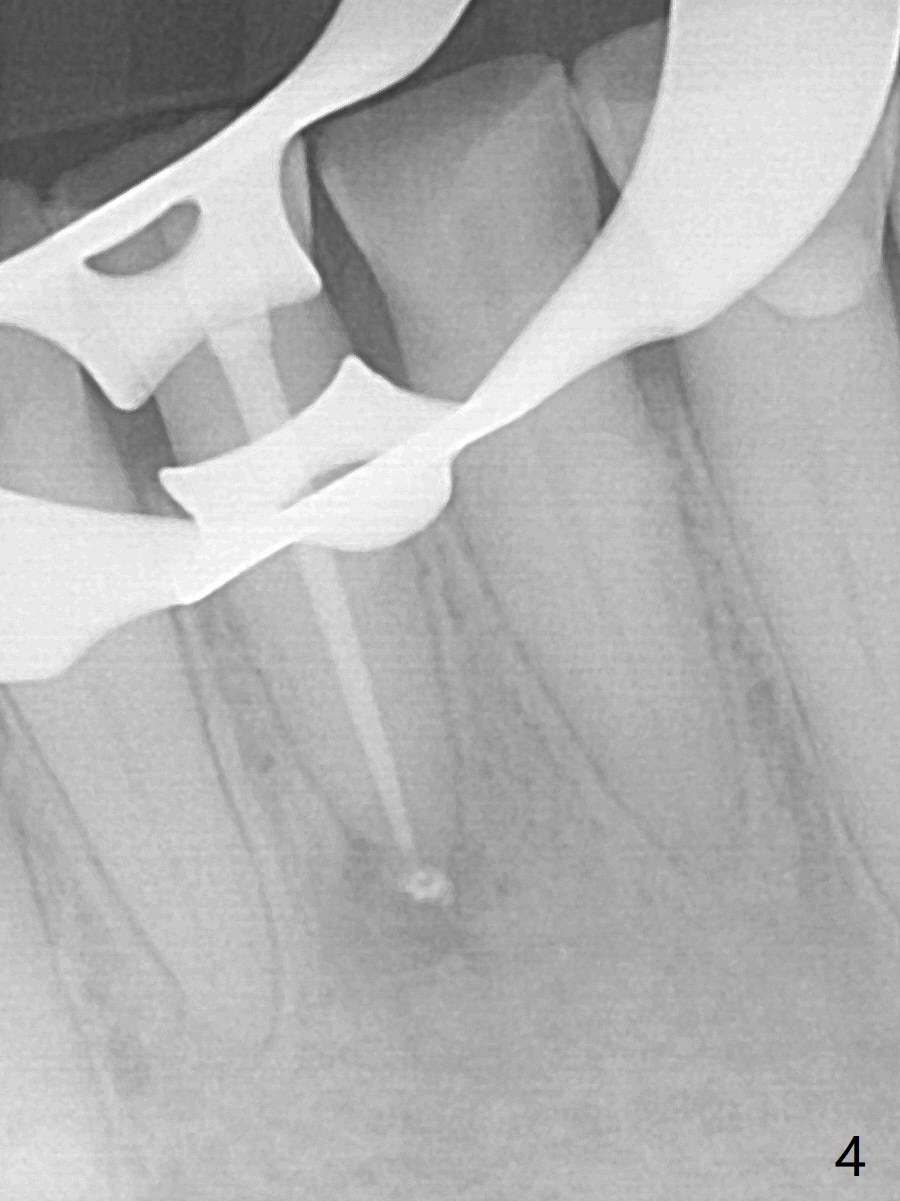

A 64-year-old man has multiple restoration and loves to eat crab. The lower incisors have severe wear. The tooth #25 is discolored with pulpal exposure and periapical radiolucency (Fig.1, 2 *). After insertion of 30/.04 master cone (Fig.3 (1 year 3 months post diagnosis)), RCT is finished with BioRoot RCS (bioceramic) and single GP (Fig.4). Nearly 10 months later, the patient returns with sinus track associated with the tooth #24 with PARL (Fig.5 *).